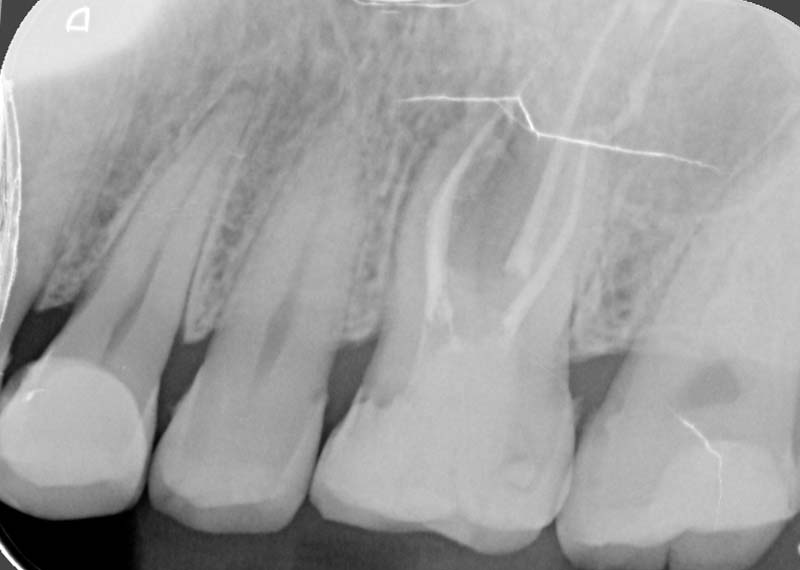

Trigger: When biting down or releasing a bite

Cause: Cracked tooth

Sometimes the problem goes deeper than what we can see. When bacteria reach the inner nerve of the tooth, it can cause persistent pain or infection.

A root canal treatment (RCT) aims to remove the infection, relieves your pain, and saves your teeth.

For: Compromised pulp (decay or cracked tooth)

We strive for single visit whenever possible